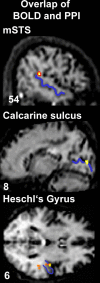

The brain should integrate related but not unrelated information from different senses. Temporal patterning of inputs to different modalities may provide critical information about whether those inputs are related or not. We studied effects of temporal correspondence between auditory and visual streams on human brain activity with functional magnetic resonance imaging (fMRI). Streams of visual flashes with irregularly jittered, arrhythmic timing could appear on right or left, with or without a stream of auditory tones that coincided perfectly when present (highly unlikely by chance), were noncoincident with vision (different erratic, arrhythmic pattern with same temporal statistics), or an auditory stream appeared alone. fMRI revealed blood oxygenation level-dependent (BOLD) increases in multisensory superior temporal sulcus (mSTS), contralateral to a visual stream when coincident with an auditory stream, and BOLD decreases for noncoincidence relative to unisensory baselines. Contralateral primary visual cortex and auditory cortex were also affected by audiovisual temporal correspondence or noncorrespondence, as confirmed in individuals. Connectivity analyses indicated enhanced influence from mSTS on primary sensory areas, rather than vice versa, during audiovisual correspondence. Temporal correspondence between auditory and visual streams affects a network of both multisensory (mSTS) and sensory-specific areas in humans, including even primary visual and auditory cortex, with stronger responses for corresponding and thus related audiovisual inputs.